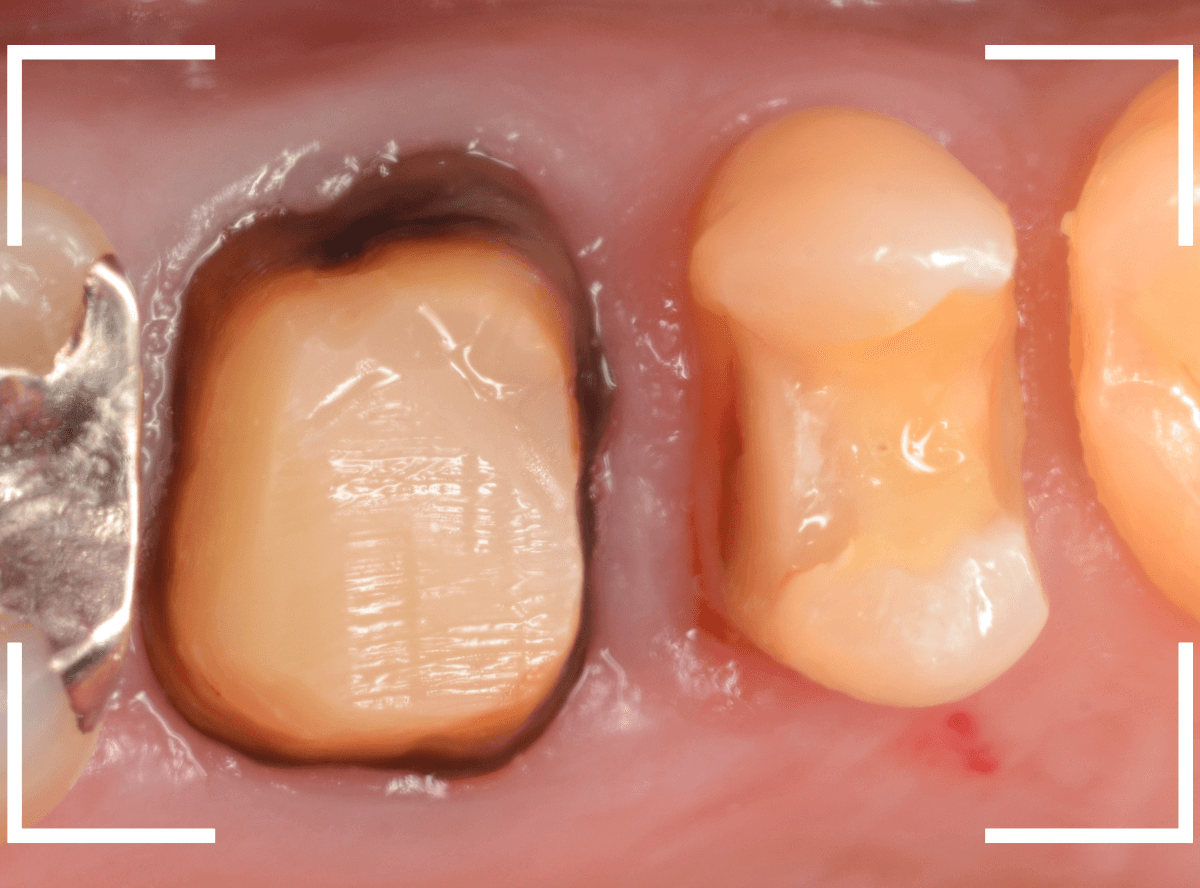

今回は、上の奥歯の銀歯(メタル・クラウン)の中で虫歯になってしまった方です。

通常は、さし歯の中が虫歯になってしまうと、レントゲンにも写らず見つけづらいのですが・・・。

歯を裏側から見たところです。

幸い、見える部分に虫歯が

さし歯と歯肉の間に虫歯ができているのがわかります。

歯の奥まで虫歯が進んでいるのか、浅い虫歯ですんでいるのかは治療をしながら調べていく必要があります。

さし歯を外すと、金属の土台(メタル・コア)が出てきました。

慎重に土台を外して、中を調べます。